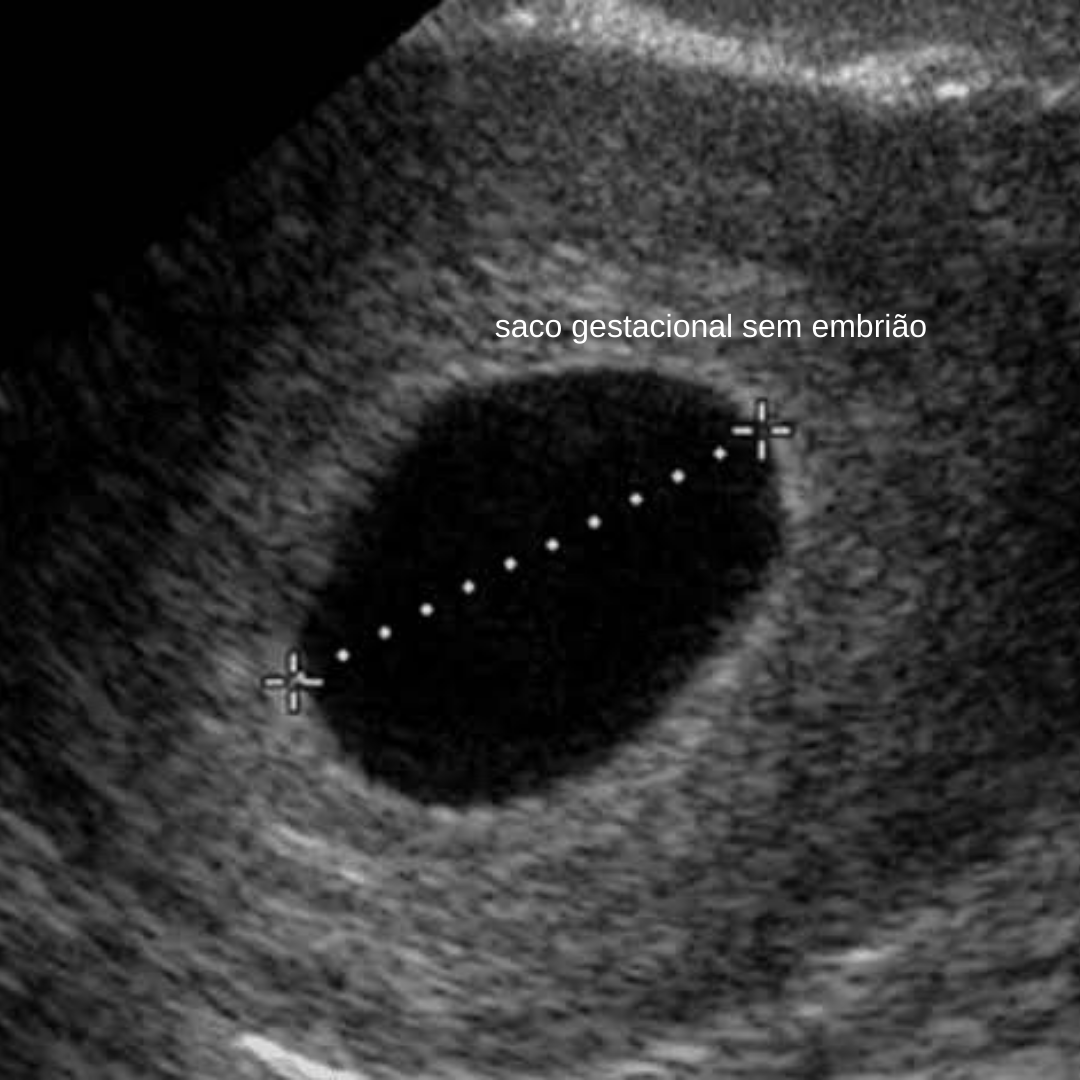

Es en este momento ecográfico donde se encuentra un saco gestacional un trofoblasto pero no se identifica ningún embrión. El tratamiento suele ser un legrado farmacológico o quirúrgico. Suele crecer un milímetros por día.

Entenda o que é o saco gestacional o tamanho normal para cada semana e os problemas que podem surgir. El embarazo anembrionario es un problema por el cual el óvulo fertilizado se implanta en el útero y desarrolla un saco gestacional que no alberga ningún embrión en su interior. Se caracteriza por un saco gestacional de apariencia normal pero con ausencia de embrión.

En palabras más simples es como si fuera un embarazo sin bebé. Con los ecógrafos más potentes y en condiciones favorables tu ginecólogo podrá verlo a través de una ecografía vaginal a partir de la semana cinco. Sac no es directamente línea media pero implantado excéntricamente. Habitualmente puede verse el saco gestacional desde la cuarta semana. Es por tal motivo que una mujer con un test de embarazo positivo y presencia de un saco gestacional intrauterino observado con un ultrasonido transvaginal es indicativo de presencia de un embarazo por lo que el riesgo de encontrar un saco seudogestacional o un quiste desidual indicativo de un embarazo ectópico es mucho menor. Conozca qué es el saco gestacional el tamaño normal para cada semana y. A gravidez anembrionária acontece quando o óvulo fertilizado se implanta no útero da mulher mas não desenvolve um embrião gerando um saco gestacional vazio.